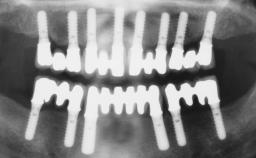

Conventional Loading of Six Implants in the Mandible and Final Restoration with a Full-Arch Metal-Ceramic FDP

# of Implants 6

Type of Implants One-Piece

Prosthesis Type FDP

Defining Characteristics Fully edentulous lower jaw to be rehabilitated with two or more implants

Modality > 4 implants, extending to mental nerve region

Bone Volume Horizontally and vertically sufficient

Defining Characteristics Fully edentulous lower jaw to be rehabilitated with an implant-borne fixed dental prosthesis

Retention Screw-retained, with 4 or more splinted implants Screw-retained, with 4 or more splinted implants